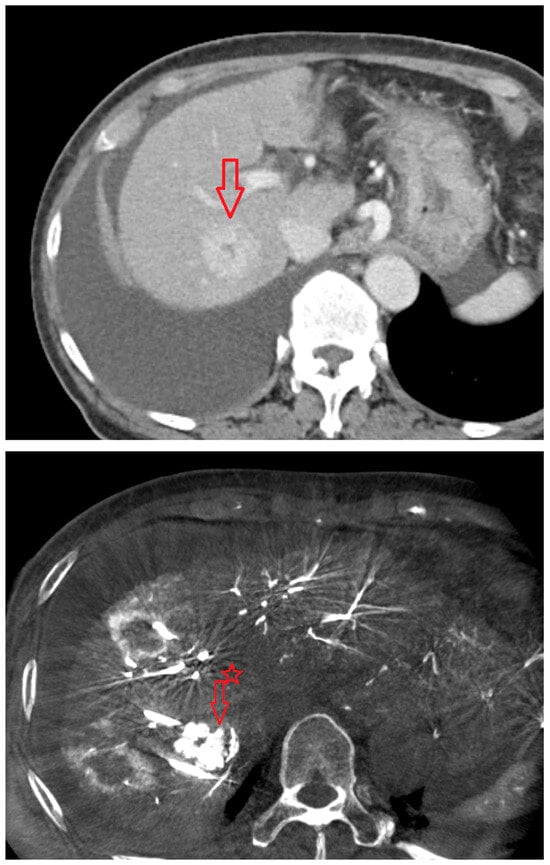

Figure 4. Images from another patient with hepatocellular carcinoma undergoing angio CBCT-guided RFA. All red arrows indicate the HCC mass. (Left): pre-procedural CT (portal phase). (Middle): pre-procedural MRI (arterial phase). (Right): intraprocedural angio CBCT. (Intra lesion − Intra background = 432.7 HU).

As shown in Figure 1, angio-CBCT allows for higher visibility of the target mass, as reflected in the ΔHU values. This can be visually confirmed in several cases. Representative cases in Figure 2 and Figure 3 demonstrate how the target mass is much more conspicuous to the operator on angio-CBCT compared to pre-procedural CT. In Figure 4, a mass, which was nearly invisible on pre-procedural CT, was identified through angio-CBCT, aiding the targeting process. Figure 5 shows a case where a mass with discordance between USG and CEUS was confirmed using angio-CBCT, leading to needle repositioning and achieving complete ablation. Finally, Figure 6 illustrates a case where a residual tumor was identified on angio-CBCT and re-ablation resulted in complete ablation.